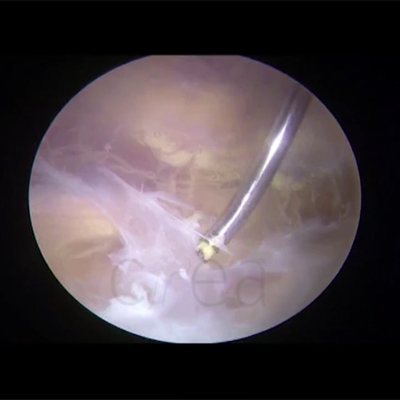

Click on an image below to view more info.